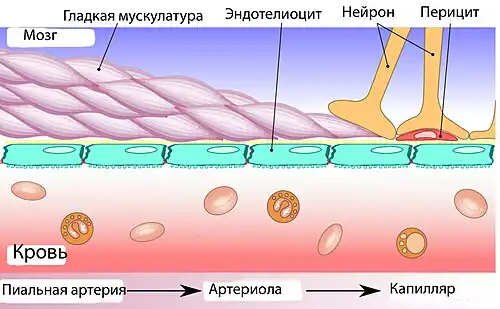

Основным элементом структуры ГЭБ являются эндотелиальные клетки. Особенностью церебральных сосудов является наличие плотных контактов между эндотелиальными клетками. В структуру ГЭБ также входят перици́ты и астроци́ты[23]. Межклеточные промежутки между эндотелиальными клетками, перицитами и астроцитами — нейроглии , меньше, чем промежутки между клетками в других тканях организма. Эти три вида клеток являются структурной основой ГЭБ не только у человека, но и у большинства позвоночных[28][29].

Эндотелий

Капиллярные сосуды выстланы эндотелиальными клетками. Эндотелий сосудов большинства тканей содержит открытые промежутки (фенестра́ции) диаметром около 50 нм и межклеточные щели от 100 до 1000 нм. Через эти промежутки вода и растворённые в ней вещества циркулируют между кровью и межклеточным пространством. Отличительной особенностью сосудов центральной нервной системы является отсутствие как фенестраций, так и межклеточных щелей между эндотелиальными клетками[30]. Таким образом, эндотелиальная выстилка капилляров мозга является сплошной[31].

Эндотелиальные клетки полностью покрывают подлежащий белковый слой, называемый база́льной мембраной[31]. Толщина базальной мембраны колеблется от 40 до 50 нм. Она различима только под электронным микроскопом. Состоит в основном из коллагена IV типа, гепаринсульфат-протеоглика́нов, ламини́нов, фибронекти́на и других белков внеклеточного матрикса. Со стороны мозга базальная мембрана ограничена плазматической мембраной пластинчатых окончаний отростков астроцитов[9][47].

Астроциты

Астроциты — большие нейроглиальные клетки звёздчатой формы. Своими отростками они выстилают стенки мозговых капилляров со стороны мозговой ткани. В то же время, несмотря на то, что пластинчатыми окончаниями их клеточных отростков выстлано около 99 % капиллярных сосудов, астроциты не выполняют прямой барьерной функции[29][74]. Астроциты тесно взаимодействуют с эндотелиальными клетками. Между ними осуществляется постоянный обмен веществ[75]. Астроглиальные клетки индуцируют возникновение и формирование ГЭБ. При проведении экспериментов по пересадке сосудов мозга в периферические органы и наоборот — периферических сосудов в ткань головного мозга, отмечено формирование ГЭБ в периферических сосудах, пересаженных в мозг (образование плотных контактов, перестройка эндотелиальных клеток), и разобщение эндотелиальных клеток и появление фенестраций между ними при пересадке мозговых сосудов[23][76]. Также in vitro показано влияние астроцитов на фенотип эндотелия. В клеточной культуре, содержащей астроциты и эндотелиоциты, отмечено более плотное расположение эндотелия по сравнению с его чистой клеточной культурой[77].

Астроциты выделяют целый ряд веществ, которые влияют на проницаемость эндотелия[78]. Эндотелиоциты в свою очередь выделяют ингибирующий лейкемию фактор (LIF), цитоки́н интерлейки́н-6, которые воздействуют на процесс дифференциации астроцитов[78]. Расстояние от пластинчатых окончаний отростков астроцитов до клеток эндотелия и перицитов составляет всего лишь 20 нм[31][79].

Пластинчатые окончания отростков астроцитов неплотно покрывают со стороны мозга базальную мембрану сосудистой стенки с расположенными на ней эндотелиоцитами и перицитами. За счёт этого между эндотелиоцитами и тканью мозга возможна прямая диффузия различных веществ[78].